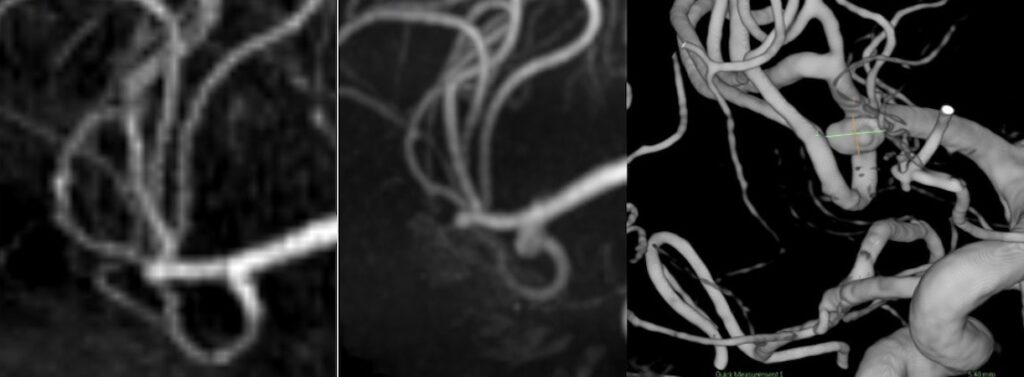

経過中大きくなってきた、5.5mm径でblebを有する中大脳動脈瘤が紹介されてきました。経過観察、血管内治療、開頭クリッピングの中からクリッピングを選択されました。